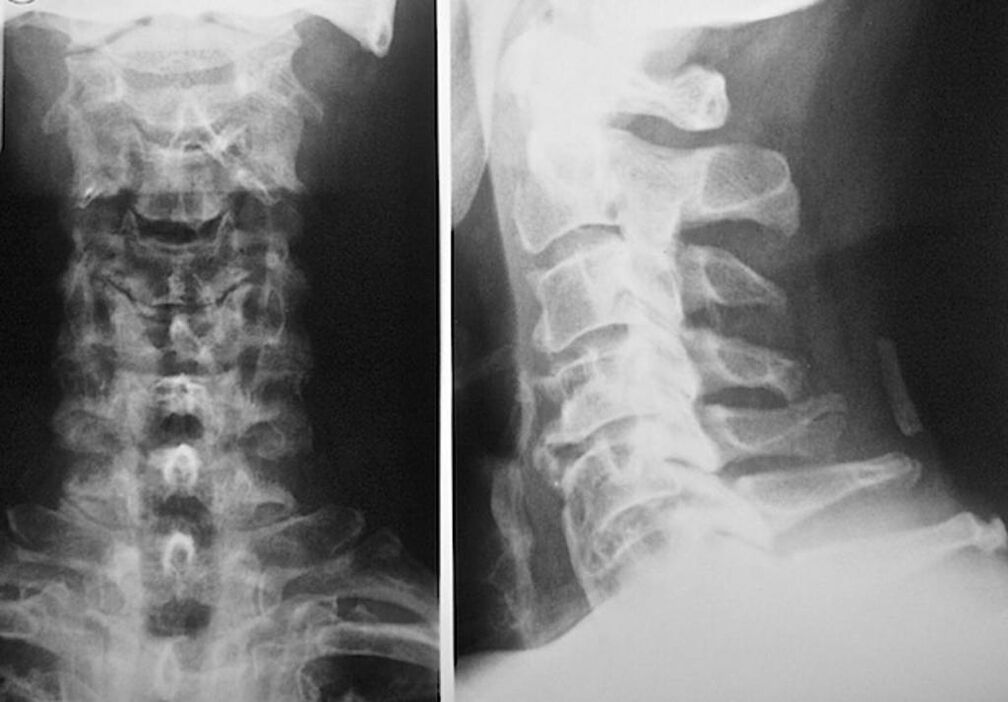

Az osteochondrosis diagnózisa: melyik orvoshoz kell fordulni

A nyaki csigolyák osteochondrosisának diagnosztizálásához és kezelésének előírásához be kell jelentkeznie egy neuropatológus és ortopéd konzultációra. A neurológus gyógymódokat írhat elő a betegség megnyilvánulásaira, amelyek befolyásolják az idegvégződések állapotát. Ennek akkor van értelme, ha a betegséget radikuláris szindróma kíséri. Az ortopéd felméri a gerincoszlop állapotát, és diagnosztizálja a további betegségek jelenlétét: scoliosis, lordosis stb.

Az intervertebrális lemezek állapotának diagnosztizálásához és pontos felméréséhez a következő kutatási módszereket alkalmazzák:

- Radiográfia.

- CT vizsgálat.

- Mágneses tomográfia.

- A nyaki erek ultrahangos vizsgálata.

Mindegyik teljesen biztonságos az egészségre, és nem fenyegeti a túlzott expozíciót. A nyaki csigolyák osteochondrosisának diagnosztizálása, amelynek kezelése az élet hátralévő részében történik, egyszerű vizuális vizsgálat után elvégezhető. Ezt bármelyik ortopéd könnyen megteheti. Kivételt képez a betegség első szakasza, amikor a nyaki régió látható patológiái nem észlelhetők.